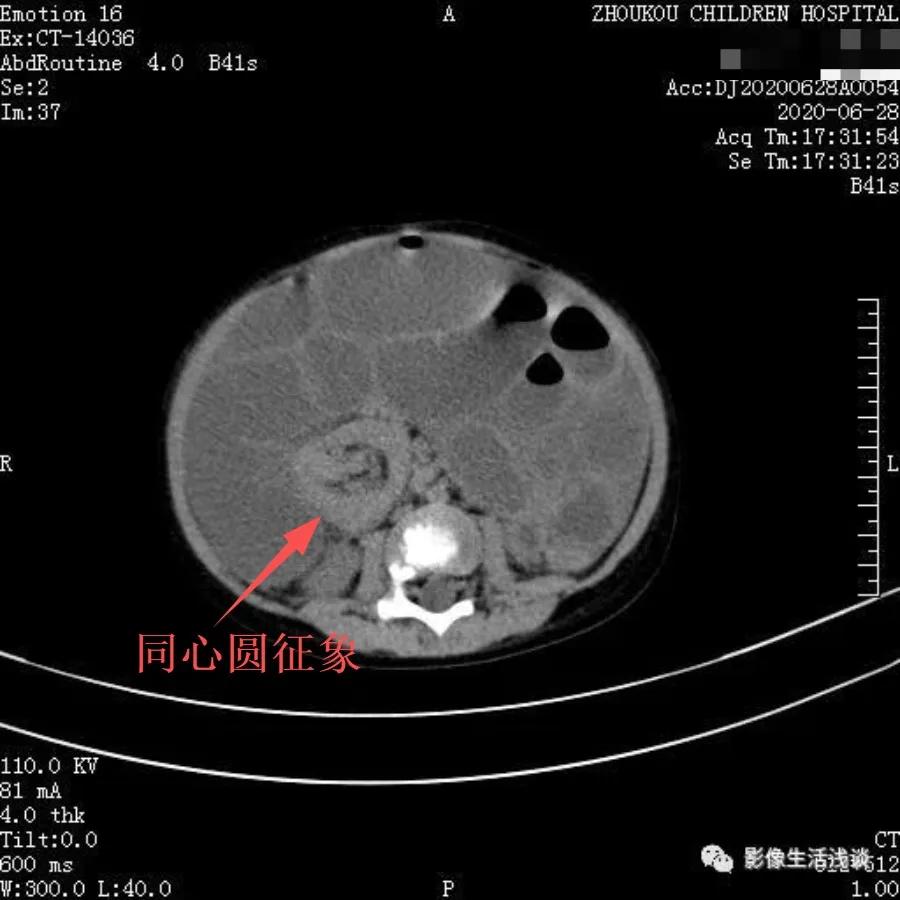

一般回肠-结肠型多见,多数患儿在不超过24小时的情况下,行透视下动态观察空气灌肠复位成功率高,小肠套叠如果套叠比较长,多数需要手术复位。下面是一例在外院以肠梗阻病人收入我院,在CT下我们可以明显看到小肠内见明显同心圆征象,肠壁局部明显增厚,肠管内见多发大小不等液气平面影,考虑小肠套叠伴高位肠梗阻,术后证实回肠-回肠-结肠套叠。